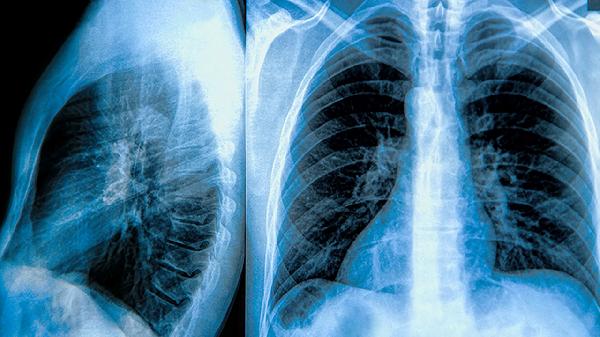

请问左肺上叶肺大泡是什么意思

左肺上叶肺大泡是指左肺上叶部分肺泡异常扩张形成的囊状结构,需根据症状和严重程度选择观察、药物治疗或手术治疗。肺大泡形成多与肺部疾病、吸烟、遗传等因素相关,长期存在可能影响呼吸功能。治疗方法包括保守观察、药物缓解症状或手术切除,具体方案需结合患者情况由医生制定。